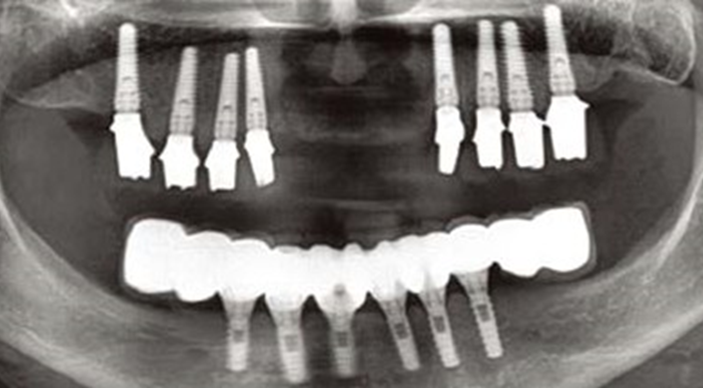

Clinical case: Full-mouth implants for mandibular & maxilla - restored using mixed prostheses

- Courtesy of Dr. Hyun Jun Kim, Korea -

Keywords

AnyRidge, full-mouth implants, mandibular, maxilla, edentulous, full mouth rehabilitation, Octa abutment, long-term clinical case, biological stability, Dr. Hyung Jun Kim

Products:

AnyRidge implant system

How can primary stability be increased?